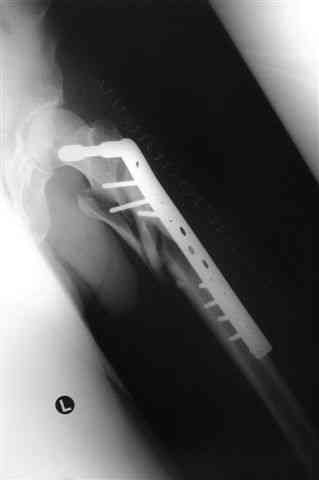

В приложении отправляю послеопер. снимки бедра и лодыжки обсуждаемого вчера больного.